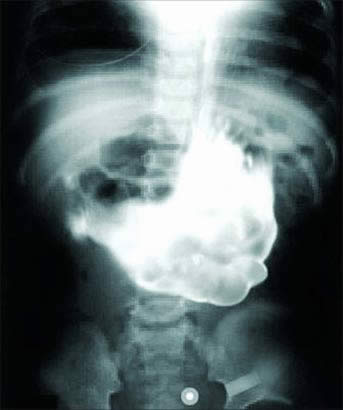

《新英格兰医学杂志》2007年11月曾报道,一名18岁的女孩因腹部不适前往医院就诊,病痛的折磨已经让她的体重锐减40磅。当医生从她的胃里取出一团10磅重的毛发时,所有人都被惊呆了。据称,女孩的腹部不适当时已经延续了5个月之久。

医生们是用一台小型摄影机发现这团毛发的,据称,当时这个毛团儿已经几乎占据女孩整个胃的容积。这位不幸的病人自称,有吞食自己头发的嗜好,也就是所谓的食发癖(trichophagia)。一开始,医生打算将毛团切割并取出,后来,却不得不采取传统的手术办法将整个毛团拿出来。